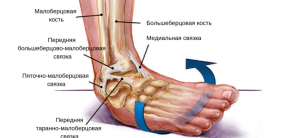

Как и чем лечить растяжение связок голеностопа

Растяжение связок голеностопа — серьезная проблема, с которой борются многие спортсмены. Это вызывает боль и дискомфорт. Его можно вылечить в домашних условиях, если вы проконсультируетесь с хирургом-травматологом. После травмы пациенту потребуется соответствующее лечение, а также длительная реабилитация. Анатомические особенности связок голеностопного сустава Голеностопный сустав — это подвижный сустав с большой свободой движений. Большеберцовая кость подвергается …